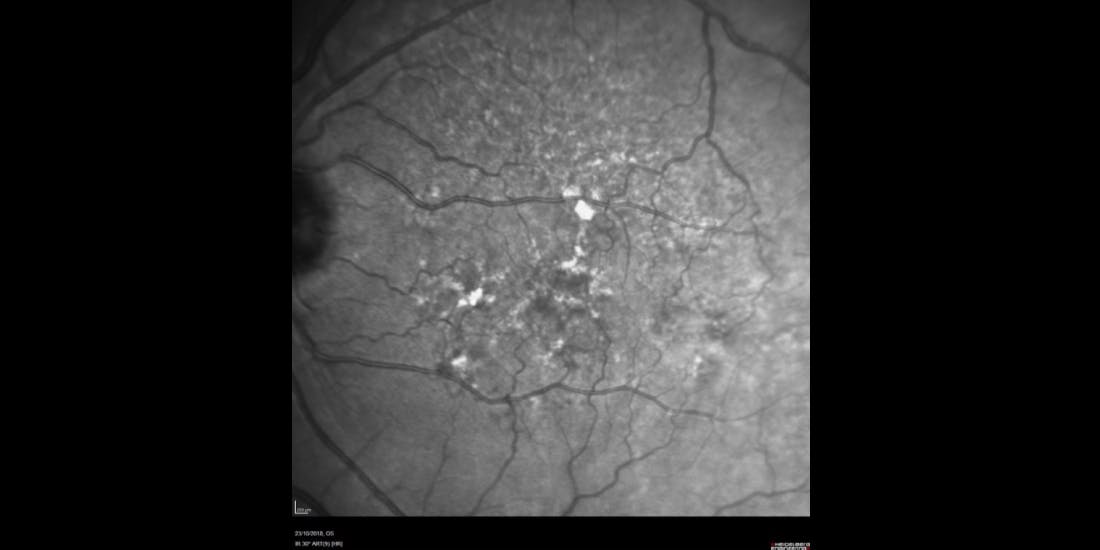

The patient was seen again in March 2023 after she had been living abroad for 5 years. No imaging had been obtained in the interim. The right eye was still under treatment for wet AMD with good anatomical response. The patient was now complaining of worsening vision in the left eye. BCVA measured 80 letters OS; low luminance visual acuity was 46 letters OS. Fundus autofluorescence (FAF) showed scattered areas of atrophy around the fovea (Figure 3). The need for more frequent follow-up to obtain imaging to evaluate the speed of progression was discussed with the patient. As well, she was advised to contact us if there were any sudden changes in vision (such as conversion to wet AMD). Finally, the patient was educated about her prognosis, specifically that she has a progressive condition and that the large drop in BCVA under low luminance indicated poor contrast sensitivity. Indeed, although the BCVA had declined only 2 letters from the previous visit, it was highly likely that the subjective complaints of much worse vision were attributable to poor contrast sensitivity.

<p>Figure 3. Blue autofluorescence taken in March 2023 showing scattered areas of atrophy around the fovea.</p>

Figure 3. Blue autofluorescence taken in March 2023 showing scattered areas of atrophy around the fovea.